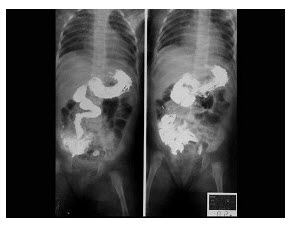

- 单项选择题女婴,出现持续性呕吐,腹胀,如图所示,最可能的诊断为()

- D